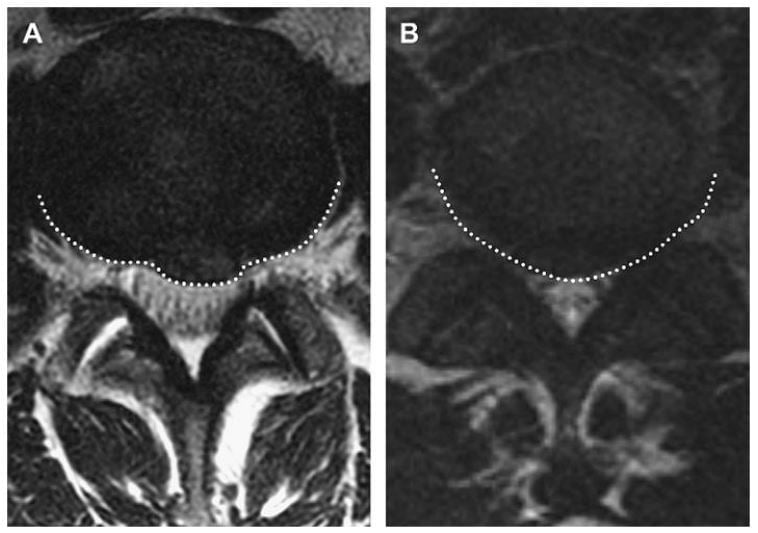

Thoát vị là protrusion nếu khoảng cách lớn nhất của các bờ chất bị lồi nhỏ hơn các bờ của chất đĩa đệm bình thường khi xác định trên cùng một mặt phẳng. Ví dụ, nếu khoảng cách trên dưới của các bờ chất đĩa đệm bị thoát vị nhỏ hơn hoặc bằng các bờ của chất đĩa đệm bình thường trên cùng một mặt phẳng (khi đo ở mặt cắt sagittal hoặc coronalđể đánh giá độ lan trên dưới), thì nó được phân loại là protrusion (Hình 3). Đo chiều trên dưới gần như luôn tốt nhất ở mặt phẳng sagittal. Lồi khu trú khi xác định trên mặt phẳng axial là phần thoát vị liên quan với ít hơn một nửa đĩa đệm (< 180 độ chu vi đĩa đệm). Protrusion có thể được phân loại thêm thành khu trú hoặc đáy rộng dựa vào mức độ đĩa đệm bị tổn thương. Protrusion khu trú liên quan với ít hơn 25% (hoặc 90 độ ) của chu vi đĩa đệm,trong khi protrusion đáy rộng nằm giữa 25% đến 50% (90-180 độ) của chu vi đĩa đệm (Hình 4).

Hình 4. Axial T2W qua đĩa đệm L4-5 cho thấy protrusion đĩa đệm. Protrusion khu trú (A) và đáy rộng (B) được vẽ bởi đường gạch chấm trắng. Protrusion khu trú liên quan ít hơn 25% (hoặc 90 độ) của chu vi đĩa đệm, trong khi protrusion đáy rộng nằm trong khoảng 25% đến 50% (90-180 độ) của chu vi đĩa đệm.